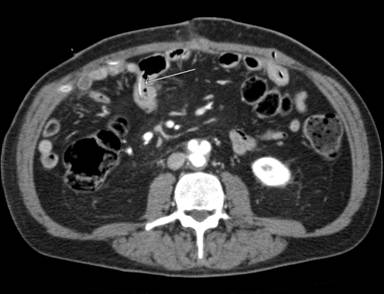

An abdominal CT scan was then performed, confirming the presence of tubular stent in the mesogastrium/right lower quadrant (Figure 1). The tube was strongly attached to small bowel loops that nearby seemed to have thickened walls. It was impossible to establish whether the tube was still intra-luminal or had migrated into the peritoneal cavity. No relevant free-fluid was detected in the abdomen.

Figure 1. After migration, stent perforated small bowel into the peritoneal cavity. (CT scan). |

As seen in this case report, a migrated stent can lead to bowel perforation. The onset can be slow and unclear if perforation does not happen suddenly. Therefore, peritonitis may be localized because of bowel adhesions that surround the perforated bowel loop. CT scan proved to be the best imaging tool to detect perforation and to describe the intra-abdominal position of the stent.